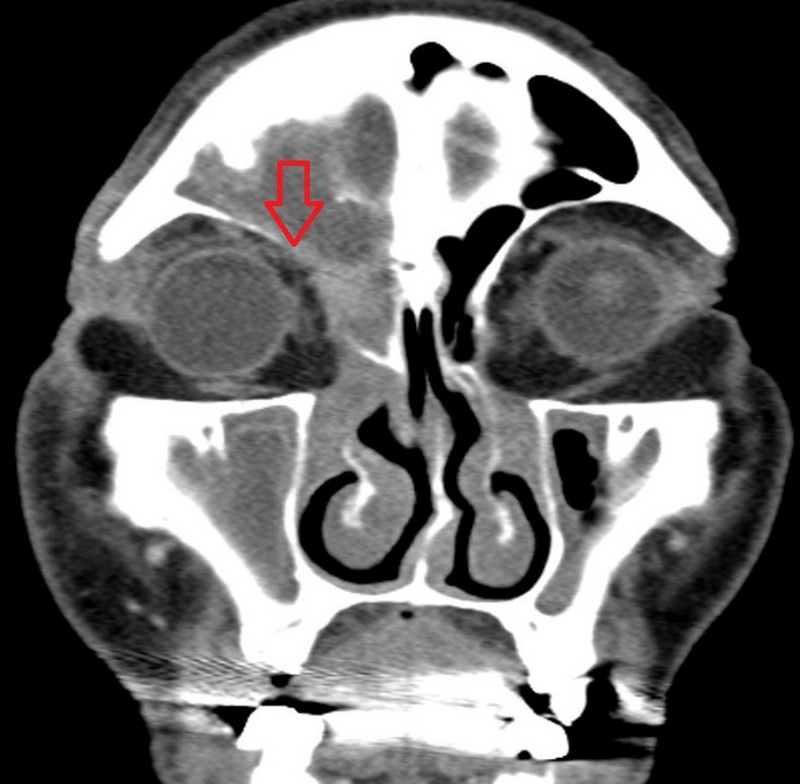

急診醫師排除是眼科的疾病後,由耳鼻喉科吳姳萱醫師收治,李先生的電腦斷層檢查結果顯示,原來是鼻竇黏膜腫脹,導致鼻竇開口阻塞,然後影響到眼睛周圍出現膿瘍的情形,診斷為急性鼻竇炎併發右眼上皮膿瘍。

電腦斷層檢查顯示,鼻竇阻塞,與眼周邊界模糊。圖/台北慈院提供